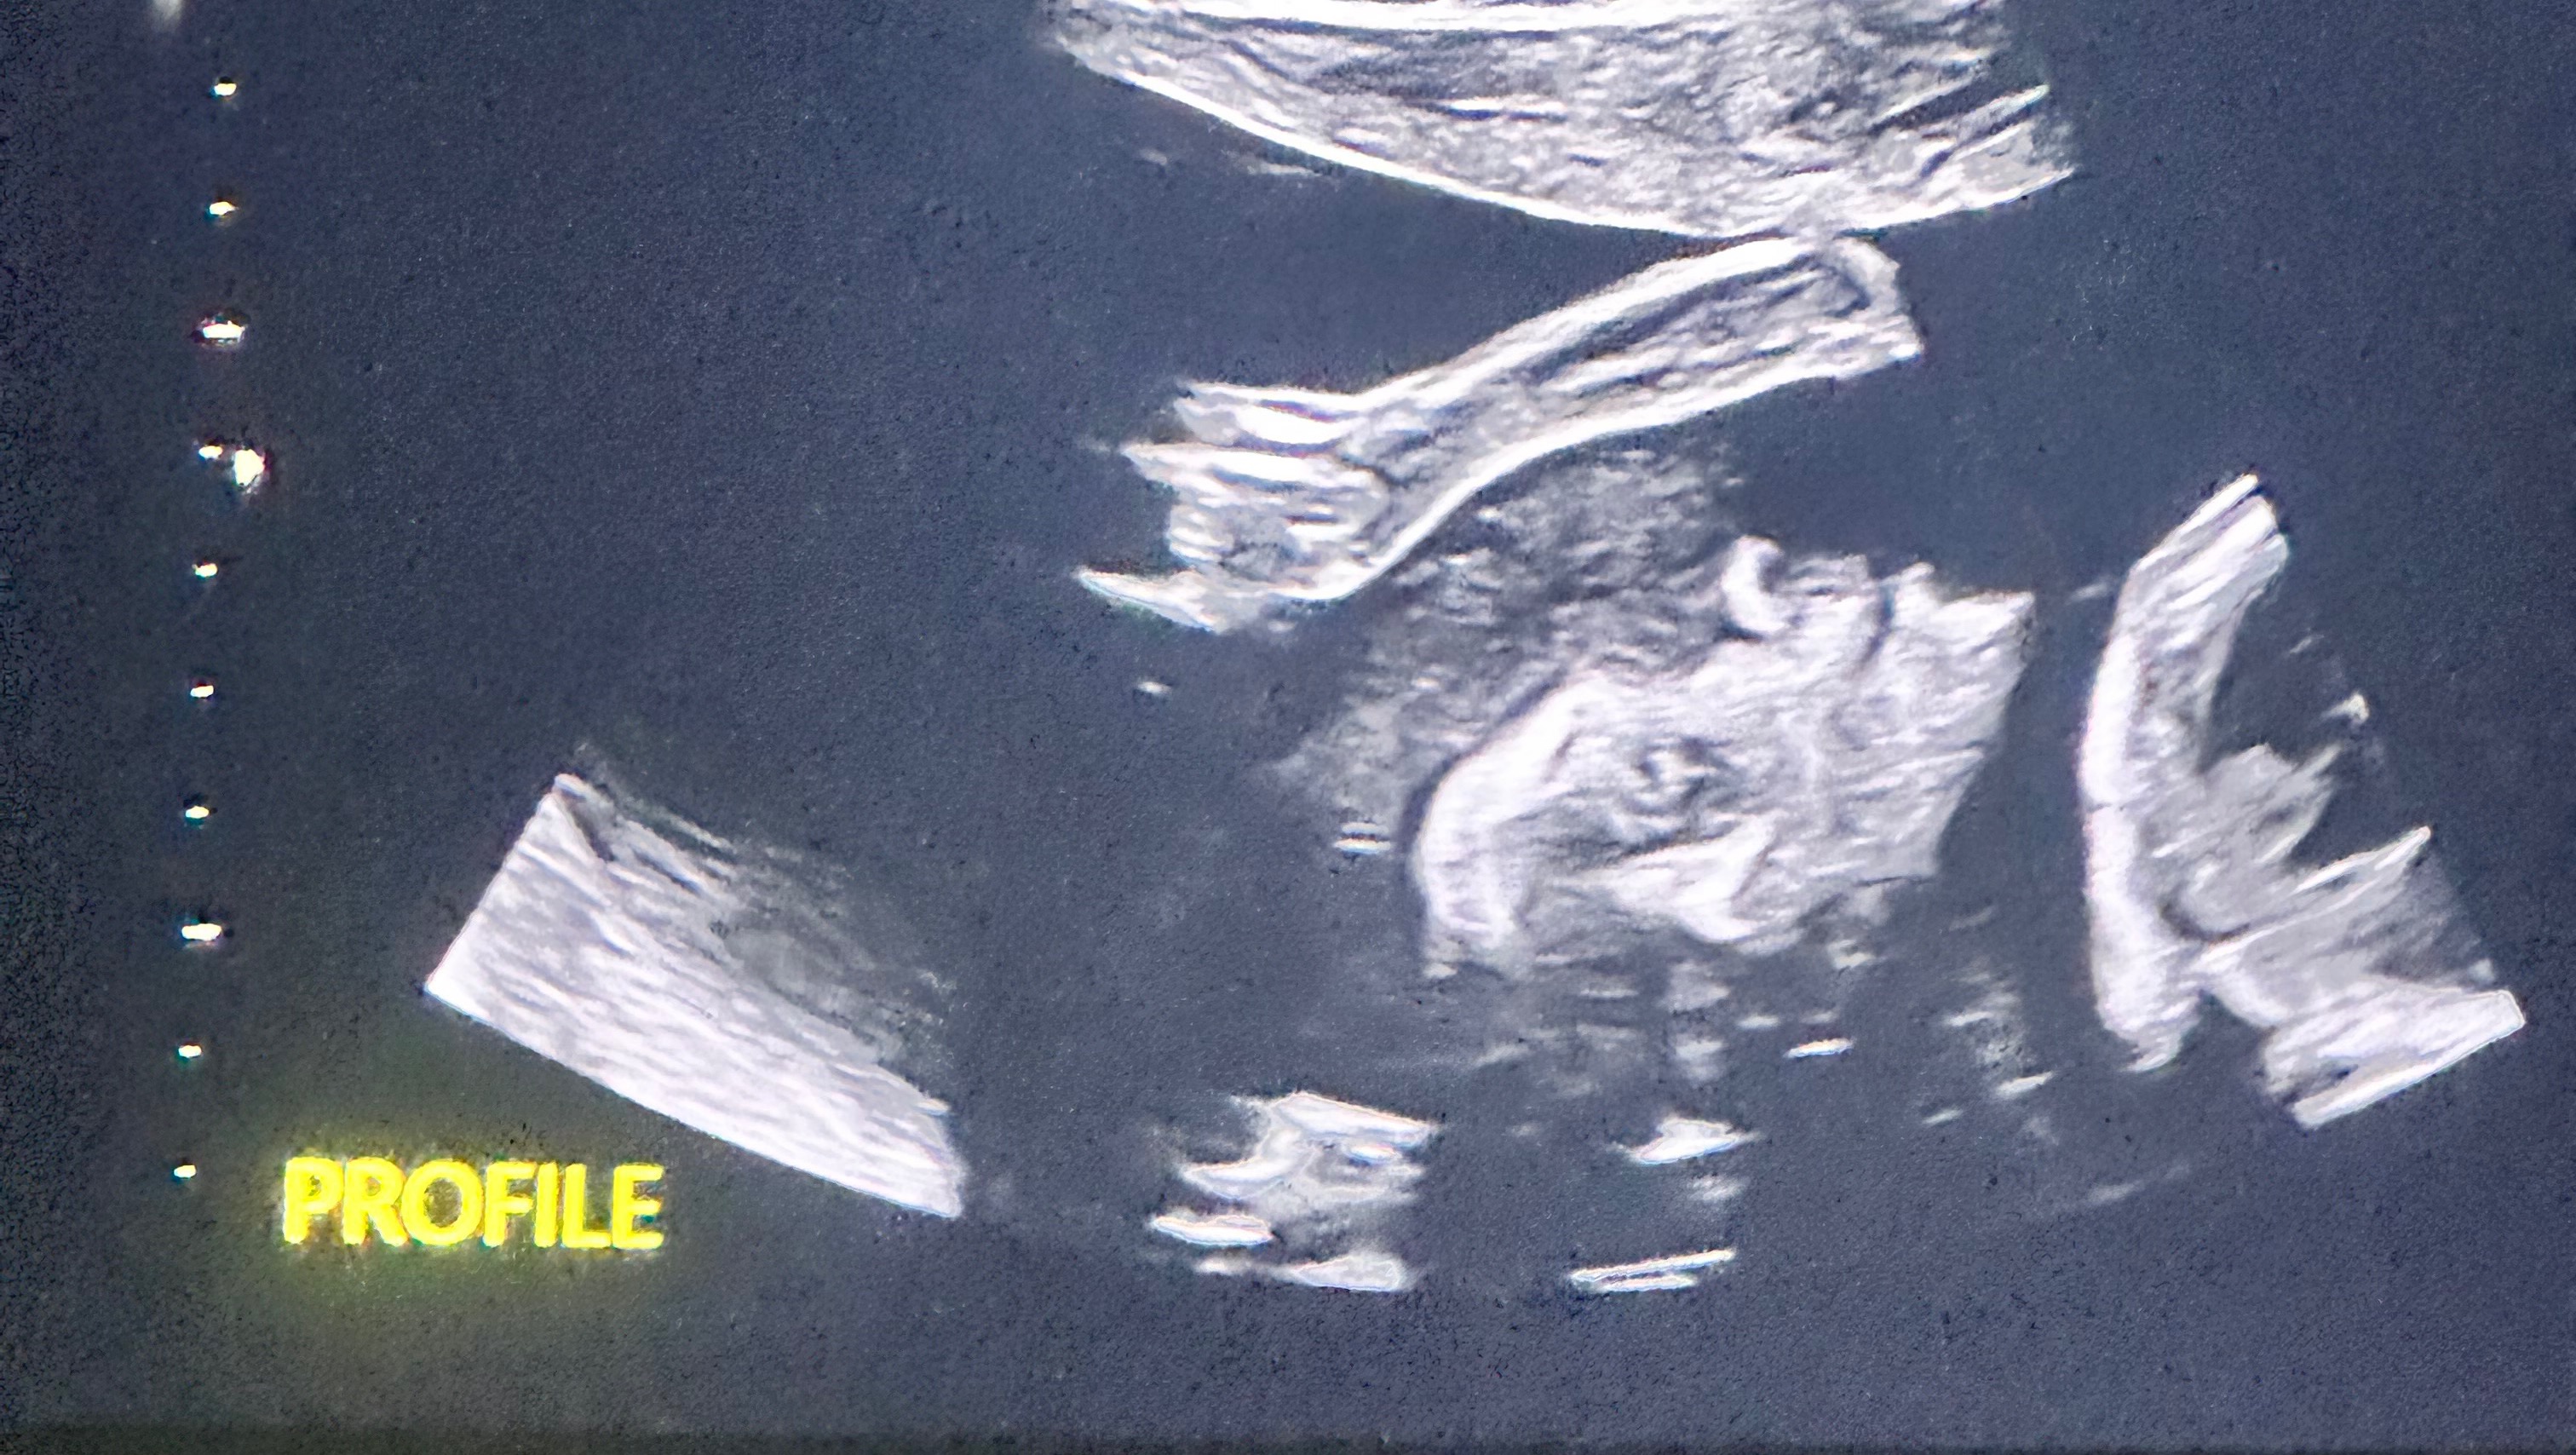

Please help my son, daughter-in-law, and grandson. July 15th, 2024 Dakota and Destinee Twyman got the news that no parent or loved one wants to hear. A fetal echocardiogram was done on their sweet baby boy who is due November 20th, 2024, and it revealed that his heart has a severe heart defect called Aortic Valve Stenosis. After learning this, the cardiologist in Bend said that Destinee and the baby would have to undergo surgery when she was around 26-28 weeks pregnant. They informed them that they needed to put a needle into the baby's heart and use a small balloon to try and stretch the value so that the blood could move correctly on the left side of his heart. The left side of the baby's heart is getting blood into the ventricle but not much can leave which causes the blood to pool up and enlarge that side of the heart. They were told that only a few hospitals could even perform the surgery with one being in San Francisco and one in Boston. The cardiologist informed them that San Francisco was able to do the surgery but the baby was in such critical condition that it had to be completed as soon as a team could be pulled together. Later that same evening they received a call from the hospital in San Francisco to let them know that the baby was in too bad of a condition and they were not willing to do the procedure and neither was Boston. They felt that if they did the surgery, the baby would have less than a 25% survival rate. After being told this had to happen, it felt like there was no hope. This is not what they had expected as newlyweds having their first child. They reached out to their local cardiologist again to search for other options. It felt like a death sentence for their sweet boy. The cardiologist said that if the baby was to be carried to full term, it would develop Hypoplastic Left Heart Syndrome (HLHS). HLHS is the worst congenital heart defect. They were referred to OHSU to talk to doctors there so that we could find out what options remained. On July 22nd, 2024 we traveled to Portland to have a new ultrasound, new fetal echocardiogram, and meet the doctors. They provided 3 options, only one of which gave him a chance at surviving. Although it is not a guarantee, they have decided to go that direction. Destinee and the baby will be monitored closely throughout the remainder of the pregnancy with many trips to Portland for testing and scans. Destinee and Dakota will have to relocate to Portland when she reaches 38 weeks. At 39 weeks she will be induced and deliver the baby in a very controlled environment with lots of teams of doctors ready to help. He will have his first surgery called the Norwood surgery within the first week of life. He will be in the hospital for around 6 weeks if all goes well. He will need another surgery called the Glenn, and then another surgery around 3 to 4 years of age called the Fontan. If all of these procedures go well he should be able to live into his teen years. Then he will need a heart transplant. For at least the 1st 6 months of his life, he will have to have continuous care and support. Dakota and Destinee will have to miss a lot of work while caring for this sweet little guy. They will be incurring a lot of expenses and could really use any help you could possibly provide. It was hard to put this all out there since they are very private people, but as we learn more about what is in store we know we have to ask for help. Please help them in any way you can, even if it is just keeping them in your thoughts and prayers. Thank you.